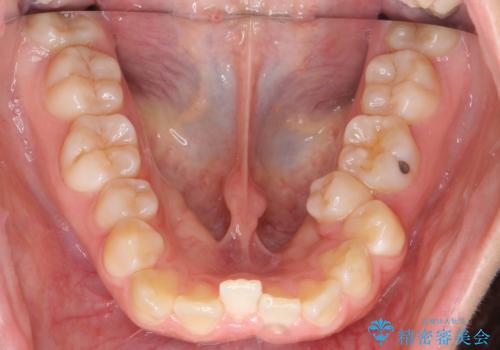

よくある悩み 前歯が裏に2本入っているのを治したい

- 前歯が2本裏に入ってしまっているのを治したいとのことでした。

最小限の抜歯により矯正ができたと、喜んでいただきました。